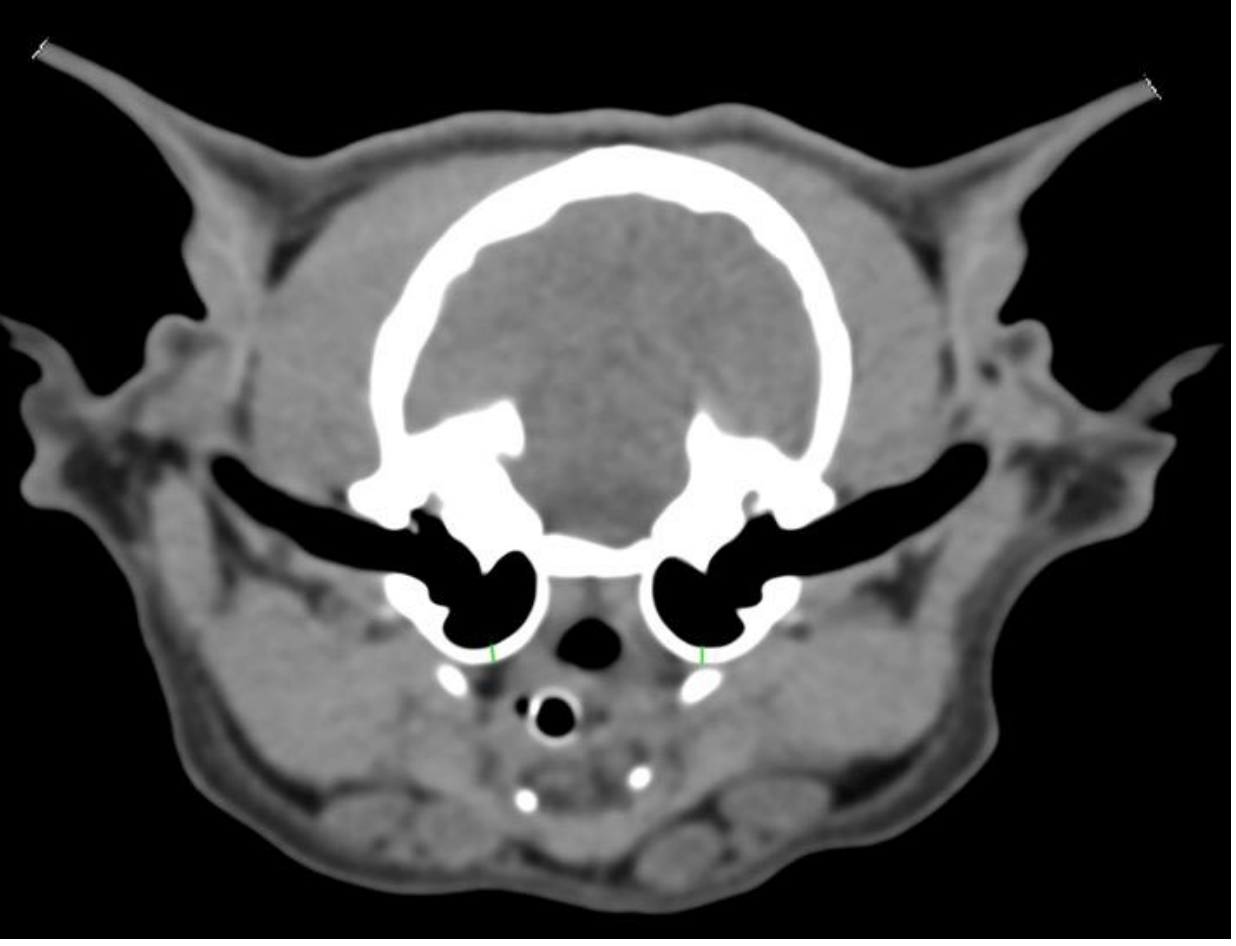

On the left, a CT image showing the measurements of the soft tissue structures within the ear canals.

In the right external auditory canal, a large, elongated soft-tissue-attenuation structure with mild peripheral contrast enhancement is observed in the horizontal portion, completely obstructing the lumen and protruding into the region of the tympanic membrane. A small amount of adjacent hypoattenuating fluid is present. The lesion measures approximately 1.3 × 0.57 cm. Moderate hypoattenuating fluid accumulation with peripheral enhancement is noted within the right tympanic bulla, with preservation of the bony wall.

In the left external auditory canal, a moderately sized, elongated soft-tissue–attenuation structure with contrast enhancement is present in the horizontal portion, smaller compared with the right side, and protruding into the region of the tympanic membrane.

Mild adjacent hypoattenuating fluid retention is also observed. The lesion measures approximately 1.0 × 0.46 cm. A discrete amount of hypoattenuating fluid is present within the left tympanic bulla, with preservation of the bony wall.